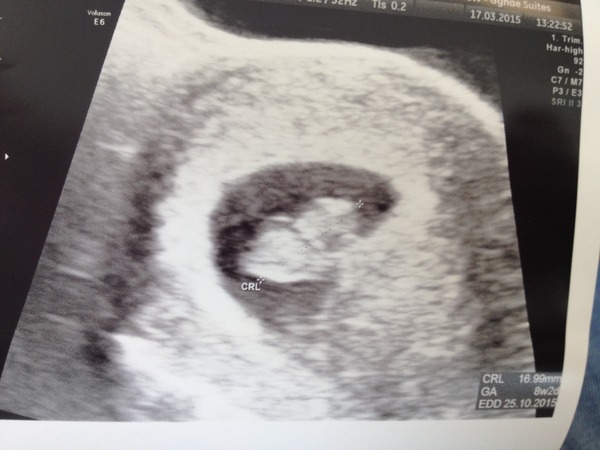

8 weeks today and my scan yippee!!!!

Choccywoccydodah · 17/03/2015 14:19

Boo!

8+2, which is what I always said! Mummy knows best Wink